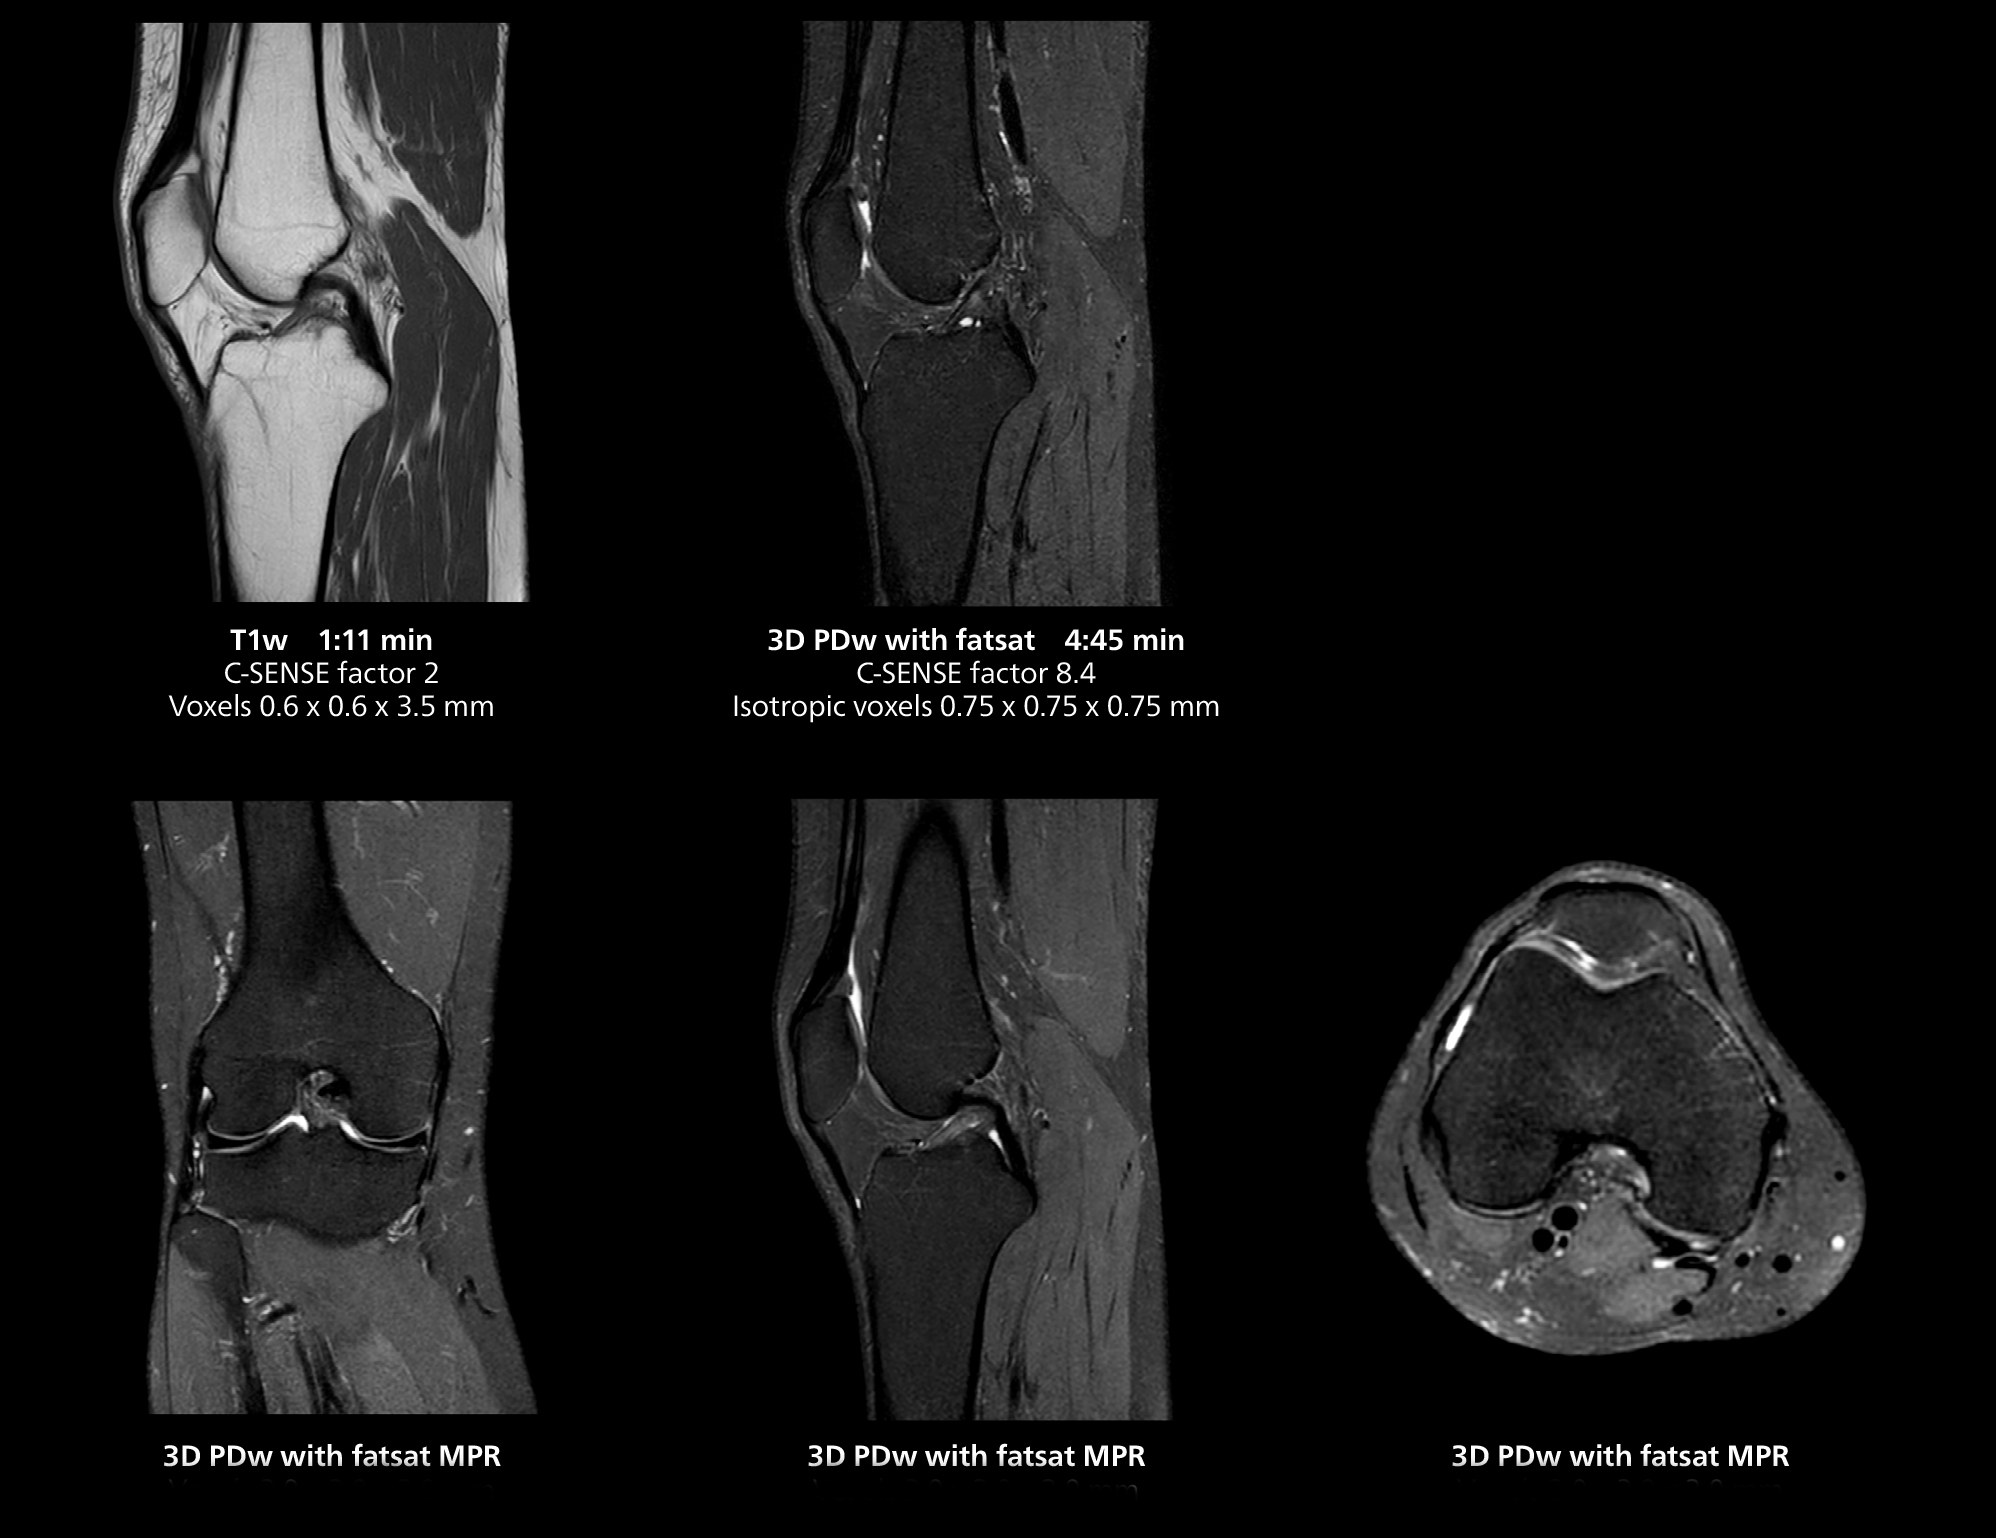

3D knee imaging

The isotropic high resolution 3D sequence in this MRI case allows for reformatting to obtain other orientations with high quality. Acquired on the MR 5300 system.

According to Dr. Gellée, the hospital conducts an average of four studies each hour, totaling about 40-45 patients per day on their MR 5300. Studies are read by approximately 50 radiologists in the Bordeaux area. Dr. Gellée is especially satisfied with the image quality of the MR system. "I obtain higher image contrast and more anatomical precision than I was used to,” she says. “When I am able to choose, I request that studies be done on this system, because I get better anatomical image quality. For example, in the knees, I can get great images of the meniscus. To me, it looks as pretty as 3T.”